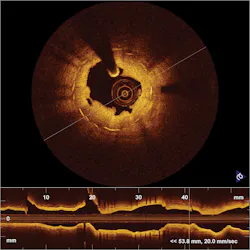

Almost from the start, the potential for using OCT in the evaluation of atherosclerosis, or thickening and hardening of the walls of medium and large arteries, was seen as a powerful application. Today, OCT is being marketed for vulnerable plaque assessment and stent visualization: In May 2010, LightLab Imaging, since acquired by global medical device company St. Jude Medical, Inc. (St. Paul, MN), announced receipt of the FDA's first clearance for a clinical OCT system to be applied to cardiovascular imaging (see Fig. 3). Competitor Volcano Corp. expects commercial release of its second-generation OCT catheter and system in Europe early this year and in the U.S. in mid-2011. Volcano plans to combine OCT and IVUS on the same catheter, and in fact has a roadmap to accomplish this.Other applications